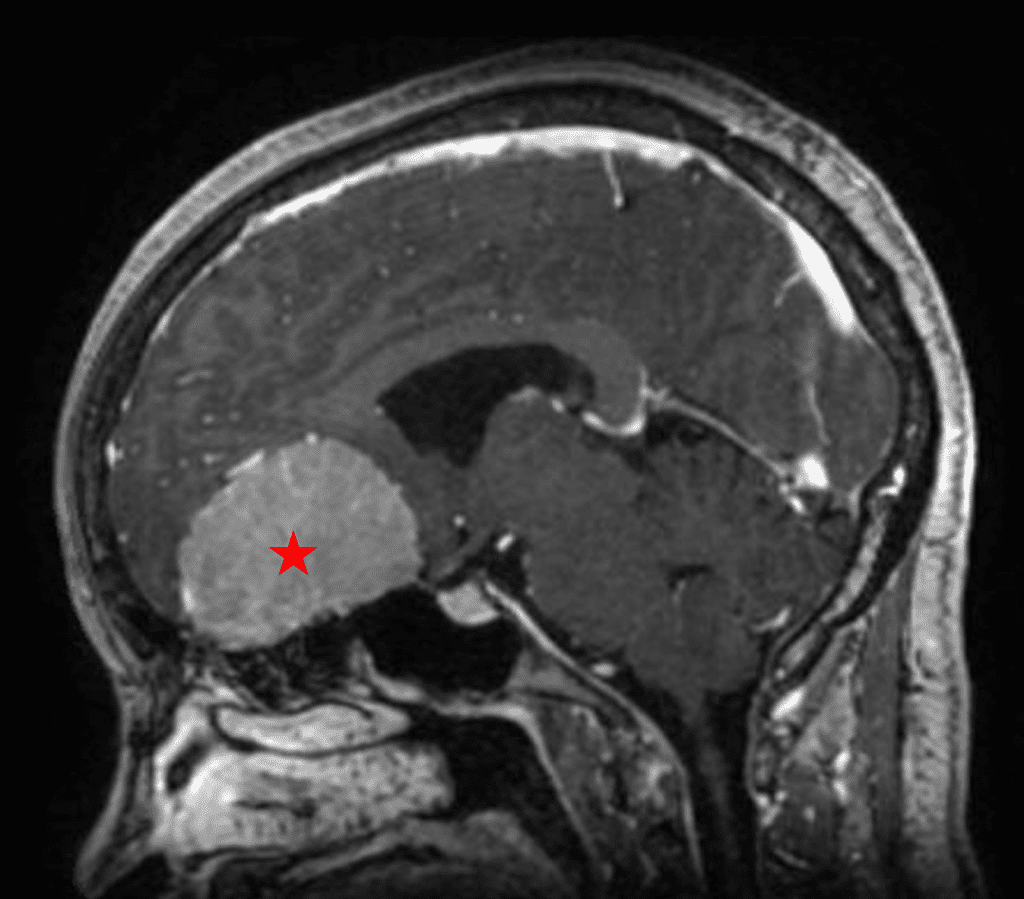

This is a 49-year-old otherwise healthy female who presented with bifrontal and retro-orbital headaches, behavioral changes, and forgetfulness. Symptoms have been progressively worsening over the past month. Her neurologic exam revealed a pronator drift, otherwise was unremarkable. MRI brain demonstrated a large extra-axial homogeneously enhancing mass of the anterior cranial fossa, resulting in significant mass effect and vasogenic edema (Figure 1a and 2a). Imaging was most consistent with a planum sphenoidale meningioma. She was referred to Dr. Xavier Gaudin for neurosurgical evaluation.

Figure 2a – Preoperative MRI demonstrating an extra-axial lesion with surrounding vasogenic edema and mass effect on the frontal lobes.

Figure 2b – Postoperative MRI demonstrating resolution of mass effect.

She was started on high-dose steroid and antiseizure prophylactic medicine. Surgical intervention was offered for mass effect, symptomatic relief, neurologic preservation, and histopathologic diagnosis. Dr. Gaudin performed a bifrontal craniotomy with complete resection of neoplasm through an interhemispheric and subfrontal approach. Postoperative imaging demonstrated a gross total resection without residual tumor and resolution of mass effect (Figure 1b and 2b). Intraoperative pathology was consistent with meningioma, WHO grade 1. She recovered very well, and was discharged home on postoperative day 3. On her follow-up outpatient visit, her preoperative symptoms had fully resolved, and her olfactory sense was maintained.